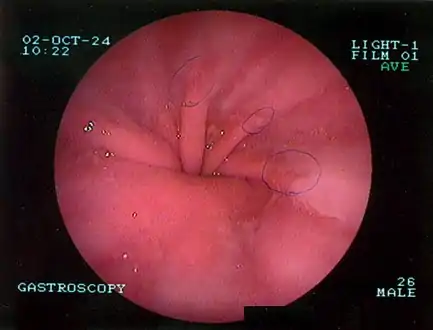

Upper GI endoscopy depicting hiatal hernia

Upper GI endoscopy in retroflexion showing Type I hiatal hernia